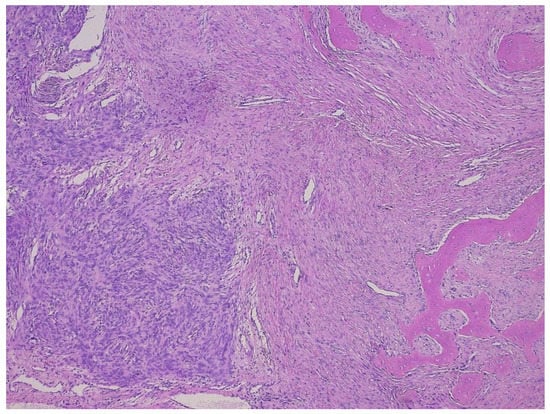

Dedifferentiated liposarcoma (DDL) is defined as the transition of WDL/ATL towards nonlipogenic sarcoma, either in the primary tumor or in a recurrence. The well-differentiated component can be absent. A total of 90% of DDL present de novo, +/− 10% of WDL/ATL dedifferentiate into DDL. Patients are most often older than 45 years. The retroperitoneum is the most frequent site (80%), and DDL is the most frequent retroperitoneal sarcoma (Figure 6). Other sites are the deep soft tissue of the extremities, the funiculus spermaticus/paratesticulum and mediastinum. The transition to the nonlipogenic sarcoma is usually abrupt and the latter most often looks like undifferentiated pleomorphic or spindle cell sarcoma, but myxoid sarcoma-like pictures, or low grade desmoid-like areas, can be seen as well (Figure 7 and Figure 8). Heterologous differentiation is present in up to 10%, myogenic (leiomyo-, or rhabdomyosarcoma) being most frequent, followed by osteo- or chondrosarcoma-like phenotypes [,]. A peculiar type is the DDL with meningothelial-like whorls and metaplastic bone formation, typically seen in the retroperitoneum (Figure 9) []. In the past, an inflammatory type of malignant fibrous histiocytoma, rich in neutrophils and also occurring in the retroperitoneum, was described. This tumor represents another phenotype of DDL []. In fact, DDL can mimic any type of sarcoma and MDM2 immunohistochemistry/FISH should be part of the panel of tests in any sarcoma occurring at any site, certainly if it is undifferentiated and pleomorphic. Thus, if one is confronted with an undifferentiated pleomorphic or spindle cell sarcoma, even if there is virtually no fat, the finding of MDM2 expression/amplification will indicate that it concerns a DDL []. An interesting but unusual form of dedifferentiation is the so-called homologous lipogenic dedifferentiation, which is characterized by big atypical lipoblasts, exactly as seen in pleomorphic liposarcoma []. MDM2 expression usually is very prominent in the dedifferentiated area as opposed to the well-differentiated part (Figure 7). Once dedifferentiation is present, the tumor gains metastatic potential but is less aggressive than other pleomorphic sarcomas. Recurrence is seen in at least 40% of cases, metastatic rates vary between 15 and 30% and tumor-related death is +/− 28% at 5-year follow-up. This figure is without any doubt much higher at 10 to 20 years []. Recent studies indicate that high grade dedifferentiation and the presence of myogenic (particularly rhabdomyoblastic) dedifferentiation correlate with a worse prognosis [,,]. As in WDL/ATL, complete surgical resection is the mainstay of treatment. DDL also harbors high level amplifications of 12q14-15, including the MDM2 and CDK4 genes. The degree of MDM2 amplification might affect clinical outcome, although prospective studies are needed to objectivate this finding []. As opposed to WDL/ATL, DDL shows other genetic changes, as 6q23 and 1p32 co-amplifications. In this respect, JUN (1p32.2) is of interest since its amplification is probably involved in the progression from WDL/ATL to DDL. Another feature that favors dedifferentiation might be the loss of HMGA2 overexpression, which is frequent in DDL []. A recent study on the integrated exome and RNA sequencing of 115 DDLs showed elegantly that gains of several somatic copy-number alternations and chromosomal rearrangements, including the DNM3OS-fusion genes and the loss of G0S2 and DGAT2, contribute to the cell cycle progression and impairment of adipogenesis [].

Figure 8.

Scar-like phenotype of a dedifferentiated liposarcoma, H&E (a), and MDM2 stain (b).